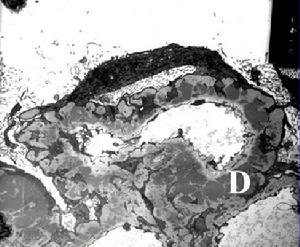

早期主要為腎小管管腔擴張,以集合小管及其他遠端小管為主。其原因主要是管腔內壓力增高而致。隨著時間的延長,腎小管上皮細胞變為扁平並漸萎縮,病變由遠端部分腎小管漸漸遷延到近端腎小管。腎小球在早期病變不明顯,鮑曼囊可以擴張,以及腎小球周圍漸漸出現炎症細胞浸潤,纖維化形成。隨著病變時間繼續延長,腎臟病變變得較為複雜,小管間質慢性炎症細胞浸潤可以更明顯,小球部分可以完全榻陷,以及硬化樣改變,腎血管也可產生類似改變。晚期因為有高血壓等等許多因素參與,腎臟病理有時與其他慢性腎小球腎炎所誘至的病變很難區別。但由於本病大部分情況下兩側病變並不一致,因此可以作為病因診斷的依據。

無論何種原因造成尿路梗阻,其基本病理改變均為梗阻以上的尿路擴張,初期管壁肌肉增厚,增加收縮力,後期失去代償能力,管壁變薄,肌肉萎縮和張力減退。泌尿系梗阻時,腎盂內壓力升高,如壓力達到相當於腎小球濾過壓時,腎小球停止過濾,尿液形成亦停止,但腎內血循環仍保持正常。這時腎內“安全閥”開放,即腎盂內的尿液可通過腎盂靜脈、淋巴和腎小管的逆流及腎盂周圍外滲,使腎盂和腎小管內的壓力稍有下降,來維持腎臟的泌尿功能,但終因梗阻未能解除,尿的分泌和回流不平衡,內壓增高繼續存在,導致腎盂擴張、積水。尿路內壓逐漸增高的同時又壓迫腎內血管,導致腎組織的缺血、缺氧、萎縮、腎小管分泌和再吸收功能下降,最終全腎積水,成為一個鬆弛的無功能的水囊。可見梗阻性腎病的病理變化由4種因素引起:輸尿管內壓力增加、腎血流減少、巨噬細胞及淋巴細胞浸潤和細菌感染。梗阻造成腎盂積水,腎盂擴張,乳頭扁平,孔外張,皮質變成薄層包圍著成囊袋狀的腎盂輸尿管。組織學顯示小管系統擴張,主要是集合管和遠端小管,近端小管亦見擴張,其壁層上皮細胞變平萎縮和小管缺血。腎小囊腔擴張,腎小球周圍纖維化,腎間質纖維化並有單核細胞浸潤。